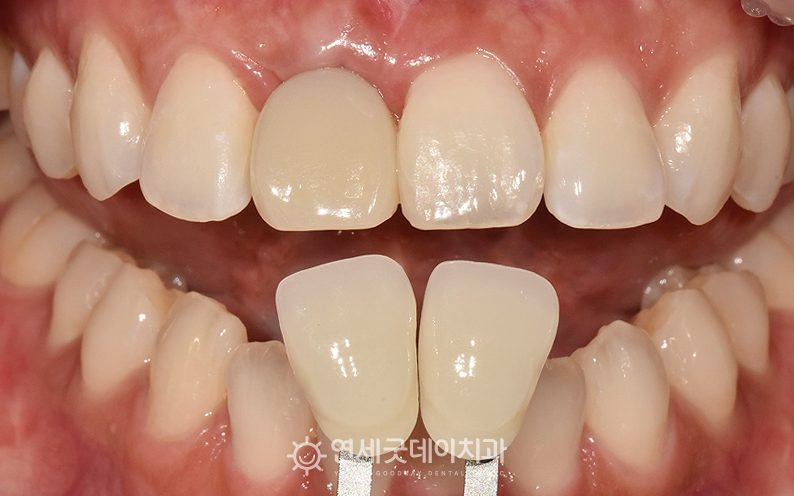

30대 앞니임플란트 치료전후

이후 지르코니아 크라운을 제작하여 치료를 마무리했습니다. 앞니는 위치상 심미적인 요소에 큰 영향을 미칩니다.